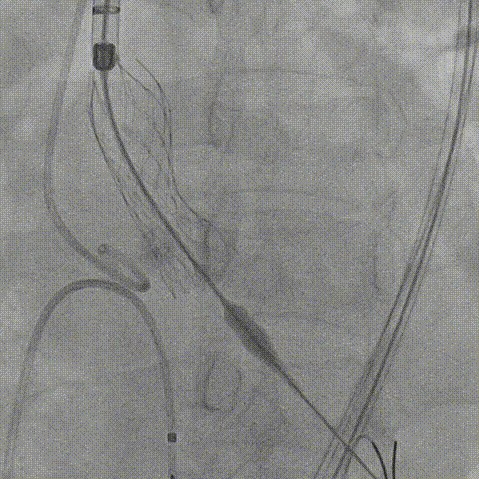

患者病史 主诉:发作性胸闷憋喘半年,加重伴呼吸困难2周。 现病史:患者半年前无明显诱因出现胸闷、憋喘,伴有下肢水肿,2周前上述症状明显加重,夜间不能平卧,痰中带血丝,为进一步诊治再次来我院,门诊以"心力衰竭"收入院。 既往史:肾功能不全、心房颤动 心脏超声提示:LVEF:0.54 1.主动脉瓣病变;2.主动脉瓣狭窄(重度)并反流(中度);3左室壁节段性运动不良;4.升主动脉扩张、双房扩大、左室肥厚;5.二尖瓣硬化并反流(中度);6.三尖瓣反流(轻-中度);7.肺动脉瓣反流;8.肺动脉高压(轻度)PGmean=105mmHg,Vmax=635cm/s,瓣口面积0.27cm²。 术前CT评估 Type0型二叶瓣,重度钙化,钙化集中在瓣叶游离缘,右冠窦为著;左冠高度11.8mm,由于左冠窦部空间较小,左冠风险较高, 升主动脉扩张,最宽处50.5mm;主动脉瓣环水平夹角61.5°,横位心。主动脉弓角77.6°,锐角弓,外周入路在腹主及髂总处有大量散状钙化,胸主处有81.6°的迂曲。 手术策略 推荐右侧股动脉为主入路,左侧股动脉为辅入路,送snare辅助过弯,使用18F大鞘,推荐预装ProStyle A® AV23瓣膜,20mm球囊预扩,初始定位对齐真实瓣环瓣上5mm超高位初始定位释放,释放过程中使瓣膜自然下滑,到工作位观察瓣膜形态,最终理想位置0-瓣下3mm。 手术过程 Step1:右侧股动脉为主入路、左侧股动脉为辅入路,成功穿刺并送入 18F 大鞘; Step2:主动脉根部造影,瓣口限制重 Step3:Type 0 型二叶瓣畸形合并重度钙化,患者瓣口狭窄严重,同时横位心,不仅导丝跨瓣困难,导管更难进入;术者凭借精湛操作,将导丝顺利跨瓣,反复微调导管角度,最终导管顺利过瓣。 导丝精准跨瓣 Step4:20mm球囊跨瓣困难,snare辅助下球囊成功跨瓣,预扩有腰无漏,冠脉充盈良好。 Step5: snare辅助下成功跨瓣,可以看到系统过弓形态瓣膜仓柔软,过弓顺滑 输送系统过弓 Step6:初始定位瓣上5mm开始释放,释放部分后观察瓣架下缘内收明显,后回收系统重新定位 初始定位 底部内收 Step7:瓣膜完全释放前,血压一度降低,术者迅速调整器械,实现瓣膜迅速锚定,快速释放 完全释放 Step8:20mm球囊后扩 最终造影,位置(瓣下3mm)形态良好 手术难点 患者不仅有主动脉瓣重度狭窄,还叠加肾功能不全、心房颤动等基础疾病,术中血流动力学波动极易引发心功能衰竭。ProStyle A® 预装干瓣“开包即用” 的特性压缩了术者操作时间,80%可回收设计给了术者容错空间,而这些看似难以逾越的难关,最终被团队精湛的医术一一化解,术中对于导丝、导管、球囊等器械每一步的精准操控,再到突发状况的从容处置,无不彰显着团队深厚的专业积淀与顶尖的操作技艺。 结语 此次手术的圆满成功,不仅彰显了陈玉国、李传保教授团队在复杂结构性心脏病介入治疗领域深厚的专业造诣与攻坚克难的决心,也充分验证了ProStyle A®系统在应对复杂高难度病例时的卓越适用性与有效性。 作为扎根齐鲁、享誉全国的医疗高地,山东大学齐鲁医院始终赓续着这片热土的仁厚文脉,将“医道从德,术业求精”的院训精神镌刻在每一次诊疗实践之中。特别是在结构性心脏病诊疗领域,医院团队始终怀揣医者担当,勇攀医学高峰,不断以更前沿的技术突破,为危重患者点亮重获新生的希望。 专家简介 陈玉国 山东大学齐鲁医院(点击查看专家详细简历) 李传保 山东大学齐鲁医院(点击查看专家详细简历) · END ·